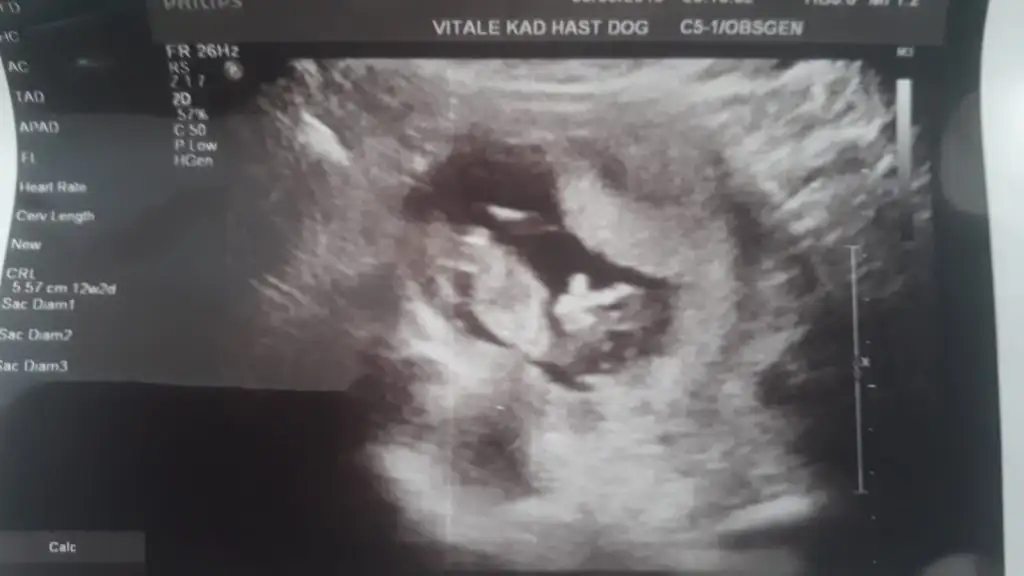

Başka usg varsa paylaşın .net degil erkek gibi. varsa usg paylaşın11 hafta iki günlük sizce nedir

Ne diyorsunuz hanımlar

Kıza gibi net usg yokmu çok net degil kaç haftalık 11 yada 12 olmalı